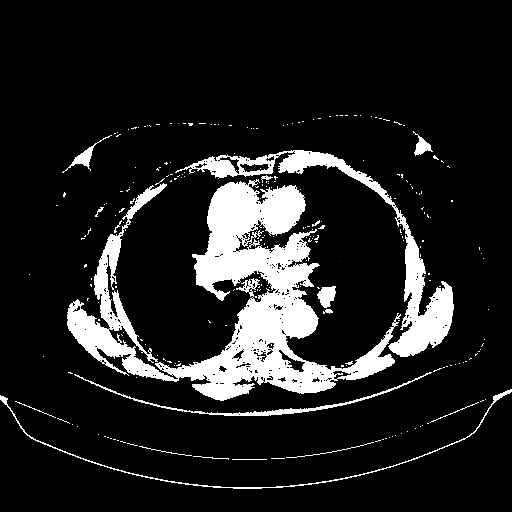

Reconstructed NATIVE CT scan (cycle consistency)

Full window (WL 1023.5, WW 4095 β†’ Low βˆ’1024, High +3071)

Actual HU range: [-1024.0, 3071.0]